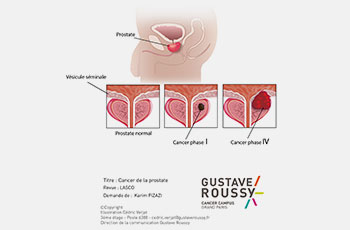

Découvrez notre collection unique d’illustrations conçues pour le domaine médical et scientifique. Chaque création combine rigueur scientifique et créativité artistique, offrant des visuels clairs et pédagogiques pour simplifier des concepts complexes.

De l’anatomie humaine aux processus biologiques, nos illustrations sont idéales pour enrichir des supports de communication, des publications académiques, des présentations professionnelles ou encore des formations en ligne.

Chaque projet est réalisé avec soin, en collaboration étroite avec des experts, afin de garantir une précision scientifique et une esthétique soignée.

Ce portfolio reflète notre passion pour la vulgarisation scientifique et notre engagement à transformer des connaissances spécialisées en outils accessibles et impactants.